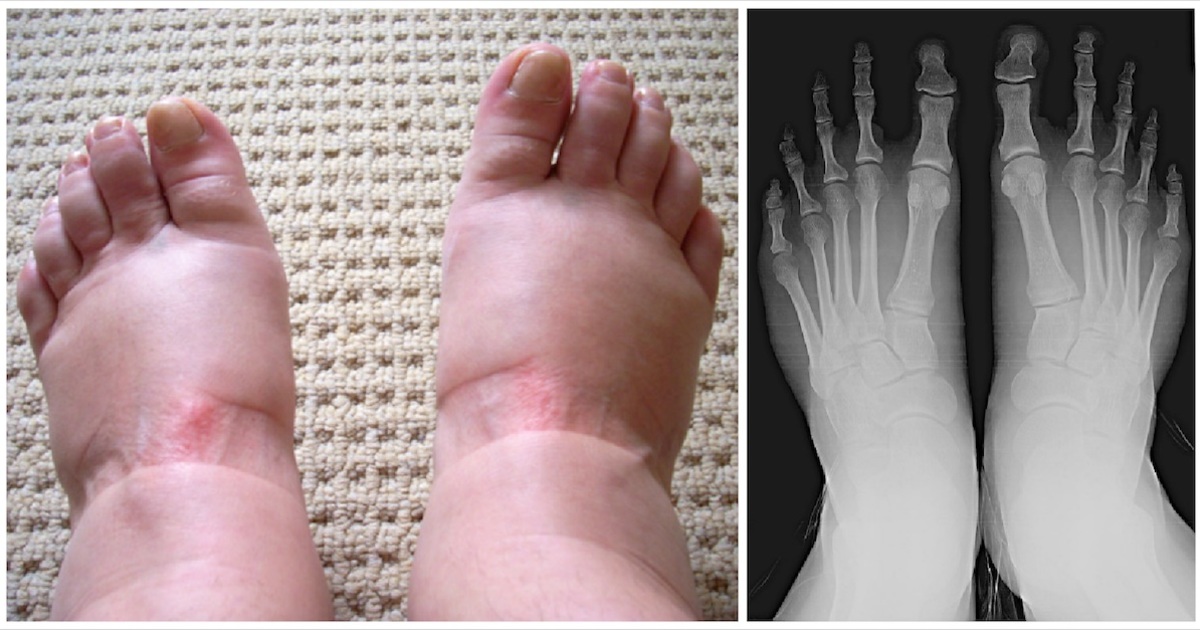

Her foot was swollen for years, she finally went to the doctor and he revealed the terrible truth

Swollen feet: 9 warning signs you must not ignore